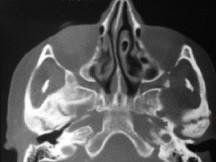

问题 关于颞下颌关节强直(如图)的描述哪项是正确的 ( )

选项 A.颞下颌关节外强直是关节外纤维黏连 B.颞下颌关节内强直是关节内骨性黏连 C.混合性下关节强直是指关节内,外强直同时发生,又称颌间挛缩 D.关节及关节周围组织器质性病变造成开口困难或完全不能开口 E.颞下颌关节强直常常突然发生